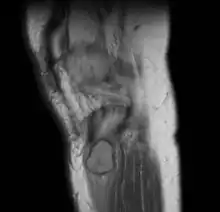

| Periosteal chondroma long bone lower leg near knee | |

Medical imaging demonstrates a well-defined lesion and erosion from pressure, with a "saucer-shaped margin", a thick intact cortex and marginal sclerosis.[1][2]